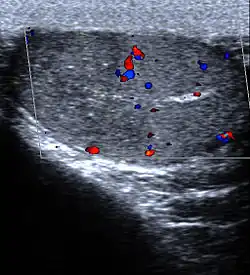

Ultrasound of segmental testicular infarction. Infarct area shown as hypoechoic and avascular upper segment of R testis.